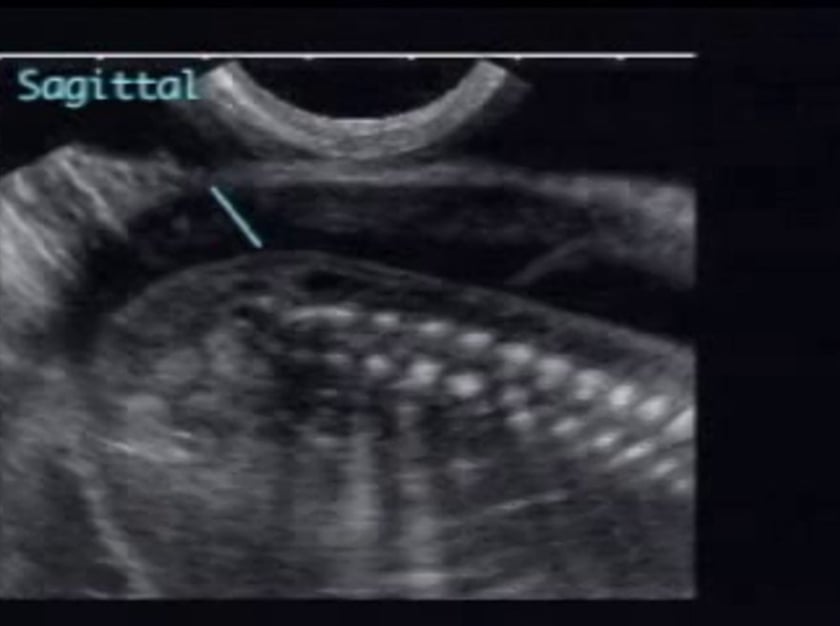

Spina Bifida ULTRASOUNDPAEDIA

Figure 8 from Neuroimaging parameters in early open spina bifida

Figure 9 from Neuroimaging parameters in early open spina bifida

[PDF] Neuroimaging parameters in early open spina bifida detection

Figure 1 from Prospective detection of open spina bifida at 1113 weeks

Figure 4 from The Diagnostic Features of Spina Bifida The Role of